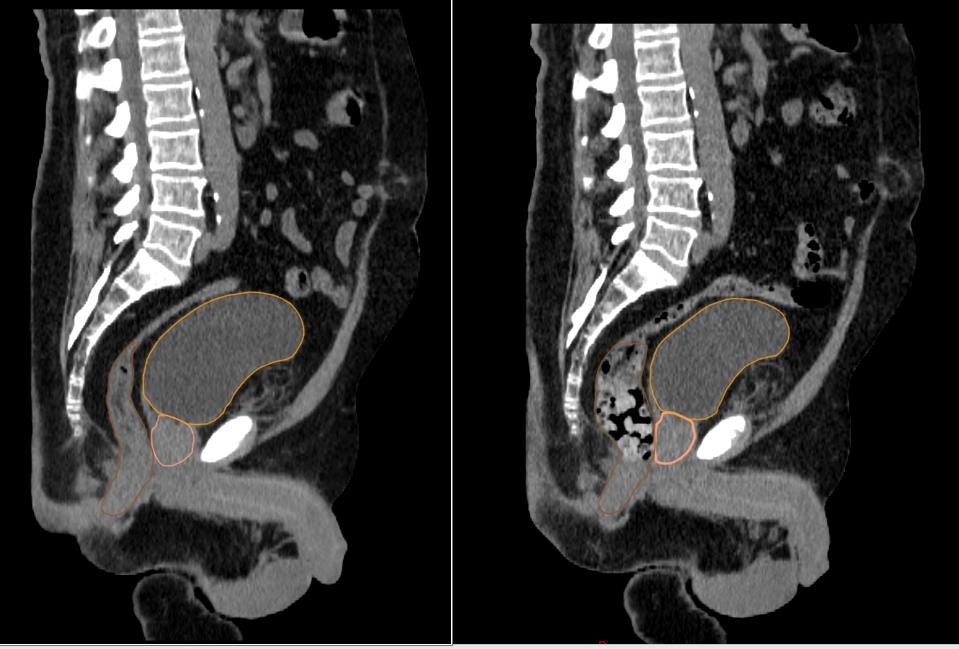

La radiothérapie adaptative consiste à adapter le traitement de radiothérapie planifié initialement, en prenant en compte les changements quotidiens dans l’anatomie du patient (déformation ou réduction du volume tumoral, amaigrissement du patient).

Contourage

Etape durant laquelle votre oncologue-radiothérapeute détermine les zones à traiter et les organes sains à protéger. Il va s’aider des différents examens réalisés. Des outils informatique d’aide au contourage peuvent être utilisés notamment via des outils basés sur l’IA (Intelligence Artificielle).

Dosimétrie

Durant cette étape, le dosimétriste va réaliser un plan de traitement sur un logiciel pour délivrer la dose prescrite à la tumeur tout en protégeant au maximum les tissus sains avoisinants. Ce traitement sera alors validé par votre médecin et un physicien médical.